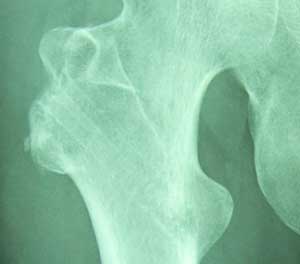

本日のレントゲンです ボルトが無くなりました(^^) ボルトが入っていたとこがうっすら分かります。 これは年単位でなくなるそうです。

着々と復旧しておりますねぇ~ これで、飛行場の金属探知機にかからなくなりますねぇ~

それがですね、ひっかからなかったんですよ! グアム旅行のときどきどきしたのですが~ 証明しようがないものねぇ